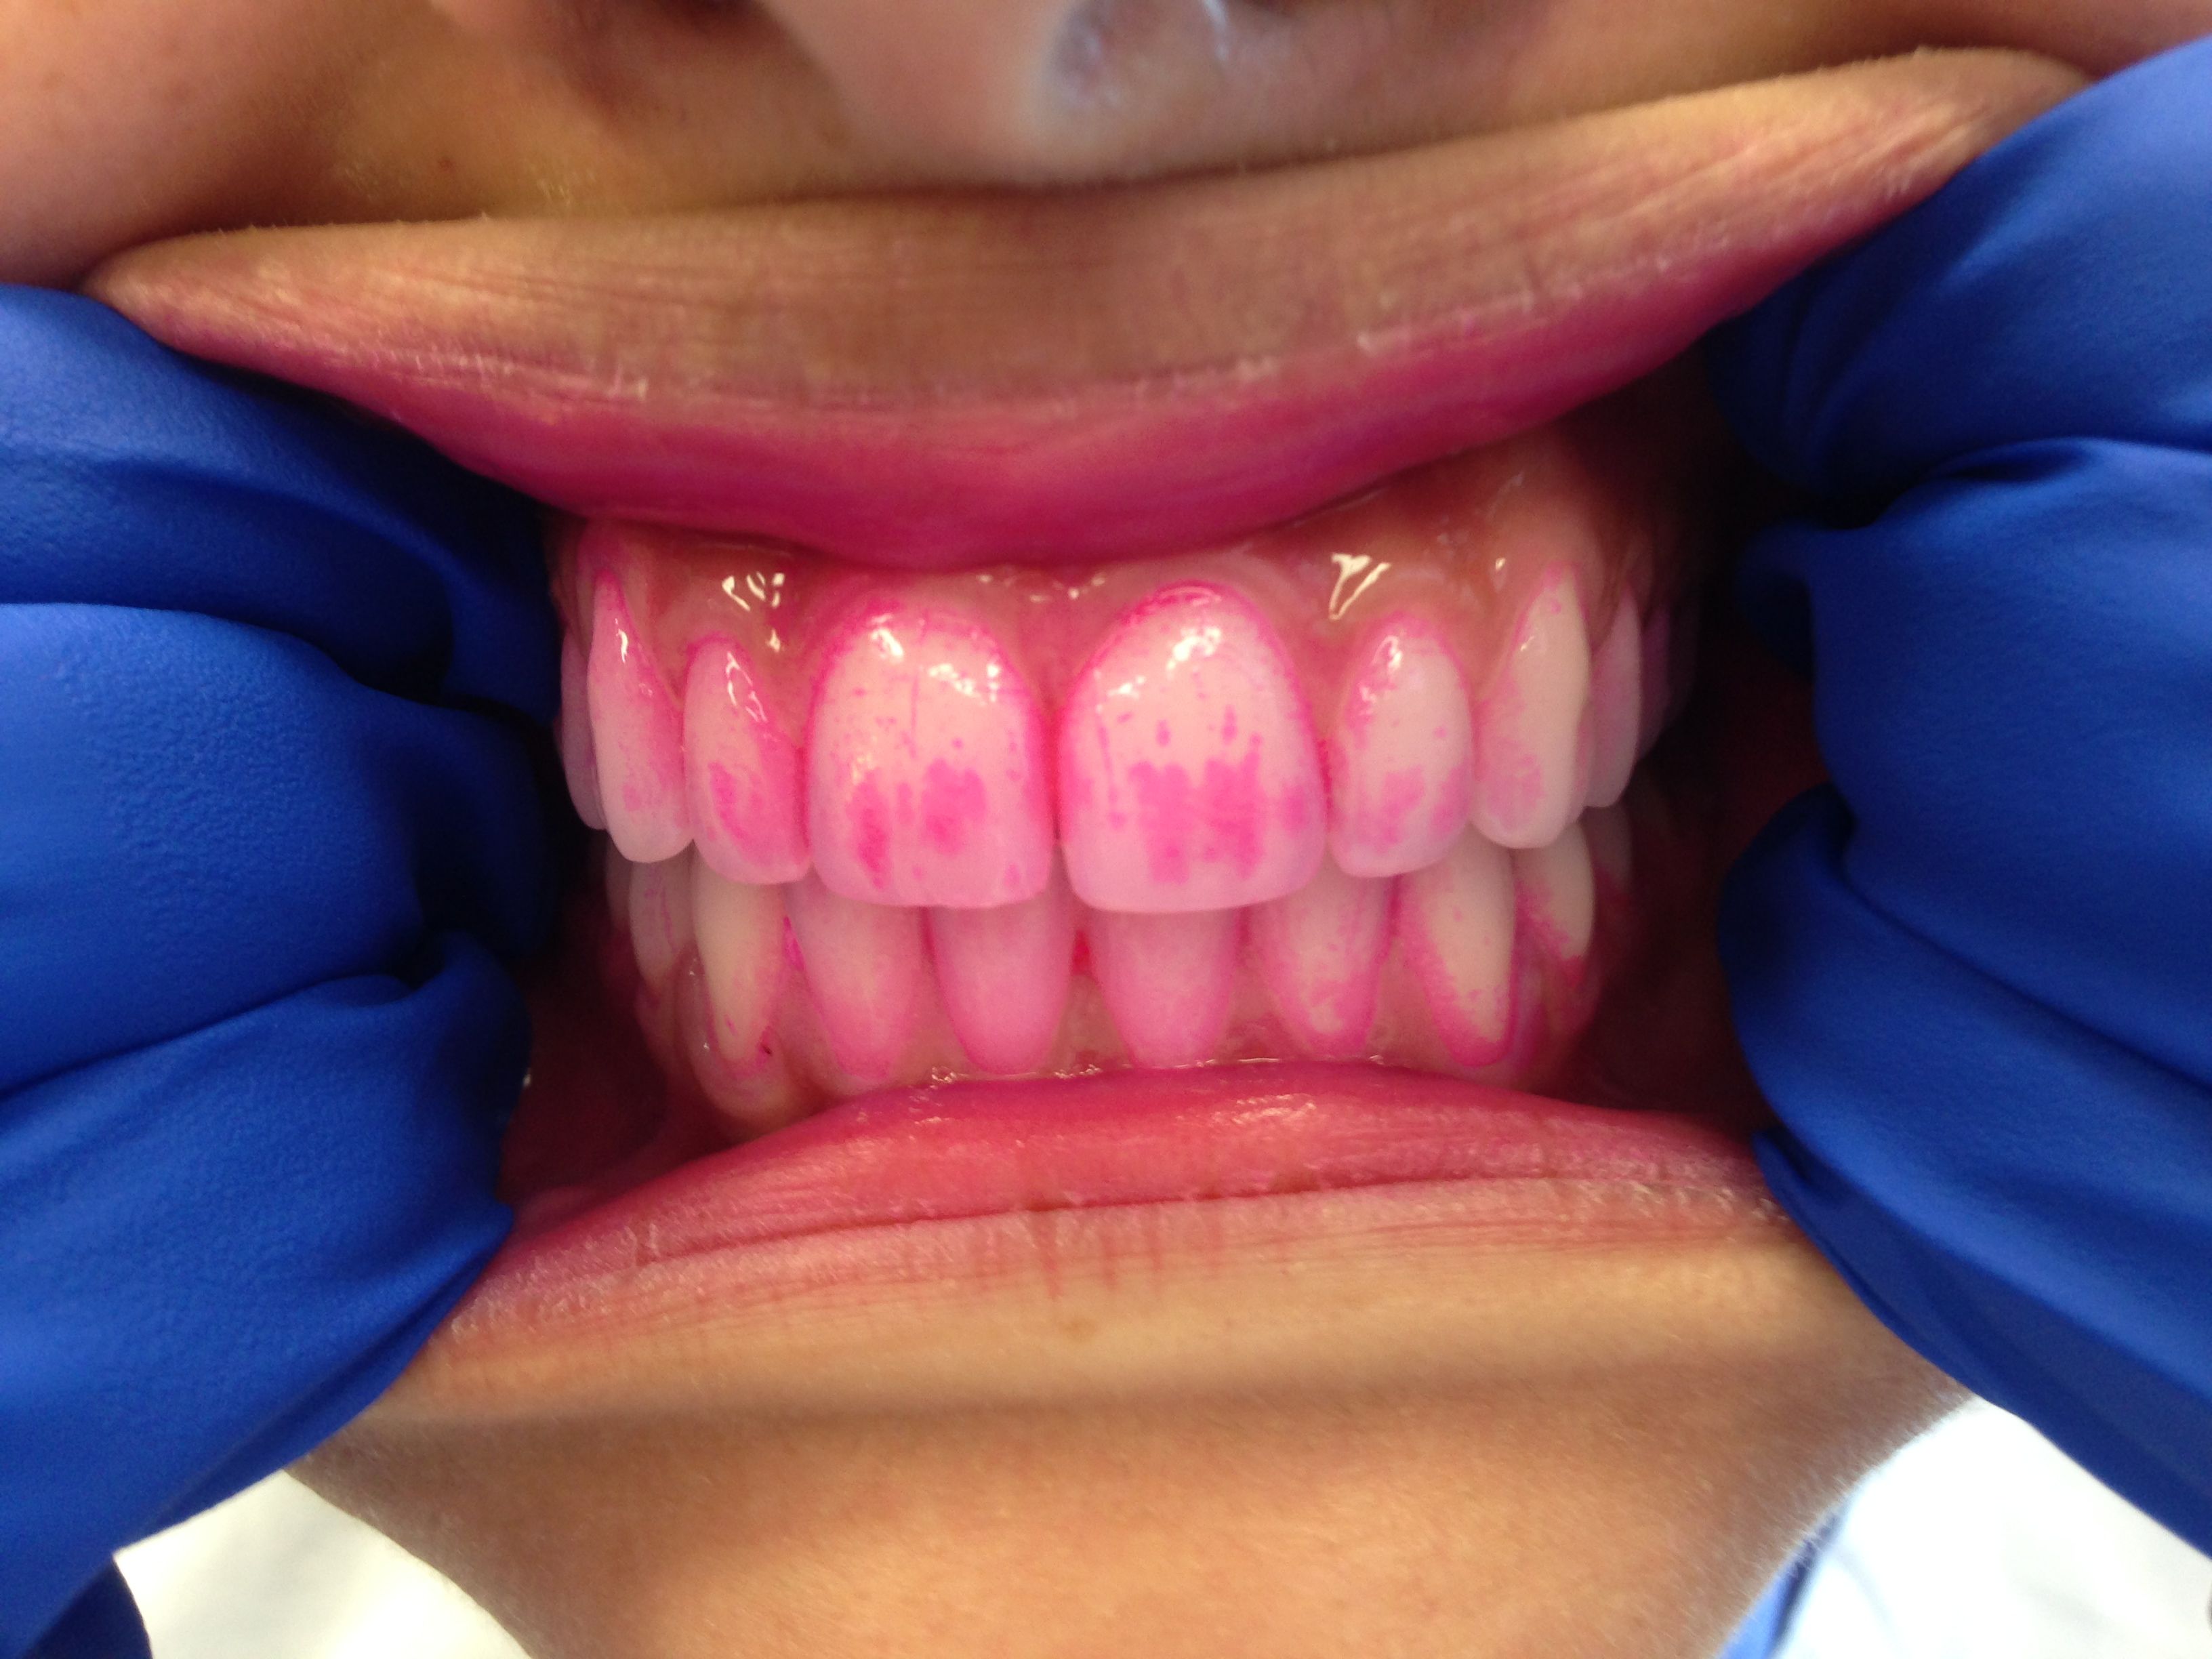

4. 치태의 검출

치태는 육안으로 확인하기 어려울 수 있지만, 치태 착색제(검출 젤 또는 정제)를 사용하면 쉽게 확인할 수 있다. 치태 착색제는 치태가 있는 부위를 붉은색 등으로 착색시켜 보여준다.[1]

치태 검출 제품은 검출제라고도 하며, 치태를 임상적으로 볼 수 있게 해준다. 치아의 깨끗한 표면은 검출제를 흡수하지 않고, 거친 표면만 흡수한다. 치태 검출 젤은 가정이나 치과에서 사용할 수 있다. 이러한 제품에 포함될 수 있는 요오드, 식용 색소 또는 기타 성분에 대한 알레르기가 있는지 일반의와 확인하는 것이 필요하다. 이 젤은 치태 바이오필름의 존재를 평가하는 시각적 보조 수단을 제공하며, 치태의 성숙도도 보여줄 수 있다.

치태 착색제는 치태 착색 젤과 유사하지만, 입 안에 넣고 약 1분 동안 씹어 사용한다는 차이점이 있다. 씹고 남은 정제나 침은 뱉어낸다. 착색 젤은 치태의 존재를 보여주지만, 치태의 성숙도 수준은 종종 보여주지 못한다. 치태 착색제는 최적의 세정을 위해 치아를 닦기 전과 후에 사용하도록 교정 장치를 사용하는 환자에게 처방되거나 제공되기도 한다. 또한 어린 아이나 특정 부위의 치태 제거에 어려움을 겪는 환자에게 유용한 교육 도구이기도 하다. 치태 착색 젤과 정제는 모든 연령대의 개인이 효과적인 치태 제거를 보장하는 데 유용하다.